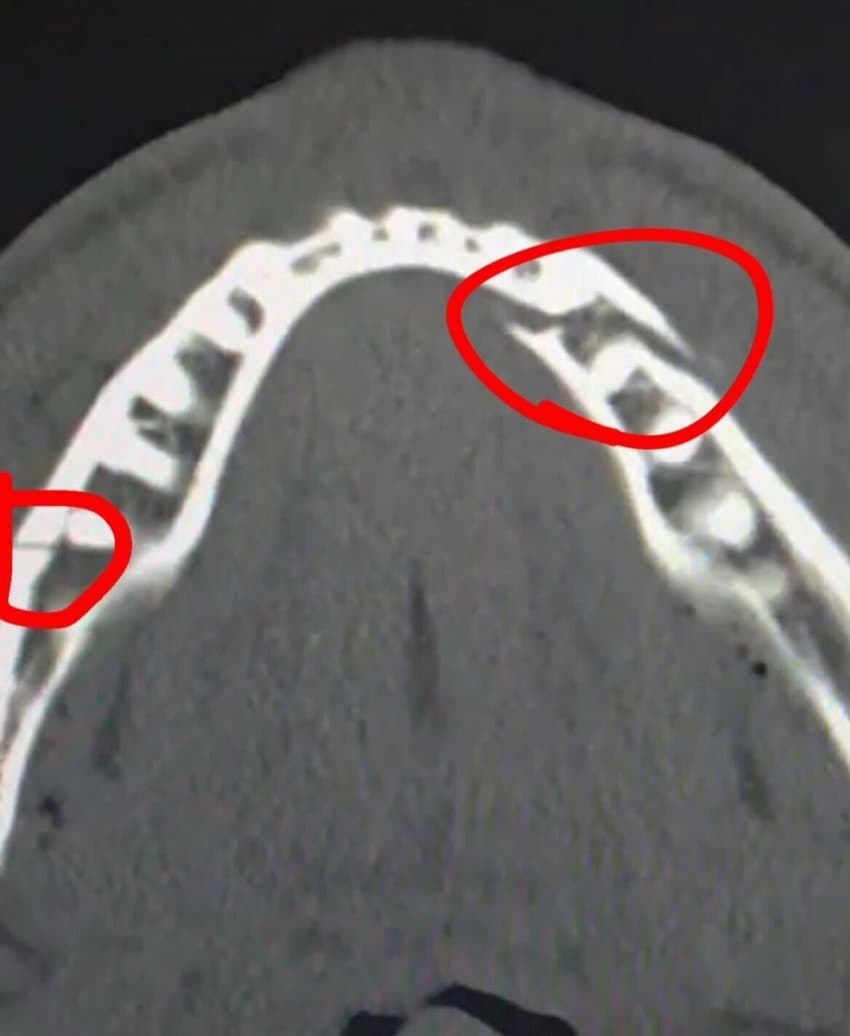

턱뼈 이중골절됨

“양쪽에 티타늄 플레이트 두 개씩을 넣었고, 치아 몇 개도 제거했다… 모든 과정은 순조로웠다. 통증과 뻣뻣함이 심하다. 7일 동안은 유동식만 먹어야 한다.”

제이크폴의 턱뼈를 박살낸 앤서니 조슈아의 주먹